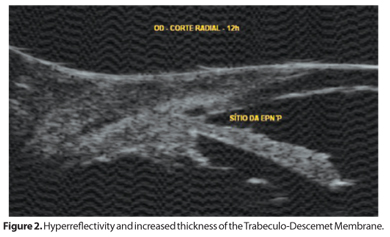

On the 5th postoperative month, the filtering bleb was slightly lower and IOP rose to 19 mmHg. UBM findings showed a hyper-reflectivity and increased thickness of the TDM (Figure 2), due to pigment deposition at the filtration site. Nd:YAG goniopuncture using free-running Q-switched mode with energy of 2.2 mJ was performed at TDM, until filtration was noted. IOP went down to 7 mmHg immediately after the procedure and then decreased further to 2 mmHg with the formation of a large and diffuse bleb. By the second month, IOP rose again to 8 mmHg. The patient was followed every other month for IOP control, which ranged from 6 to 8 mmHg for about a year, with the presence of a diffuse and healthy filtering bleb. She also underwent argon laser retinal photocoagulation for a peripheral hole, and no signs of ocular hypotony or iris synechia on gonioscopy were noted during that period of time.